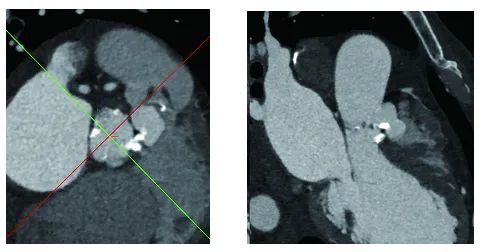

主动脉CT

主动脉根部及瓣环形态

瓦氏窦瘤形态

入路条件

该患者是严重心衰伴瓦氏窦瘤患者,同时伴有瓣叶增厚,瓣环周长经为23.8mm,左右冠高度为13.8mm和18.9mm,在瓣膜选择上需要非常谨慎。经过团队讨论决定,预装VitaFlow Liberty™ 27瓣膜。